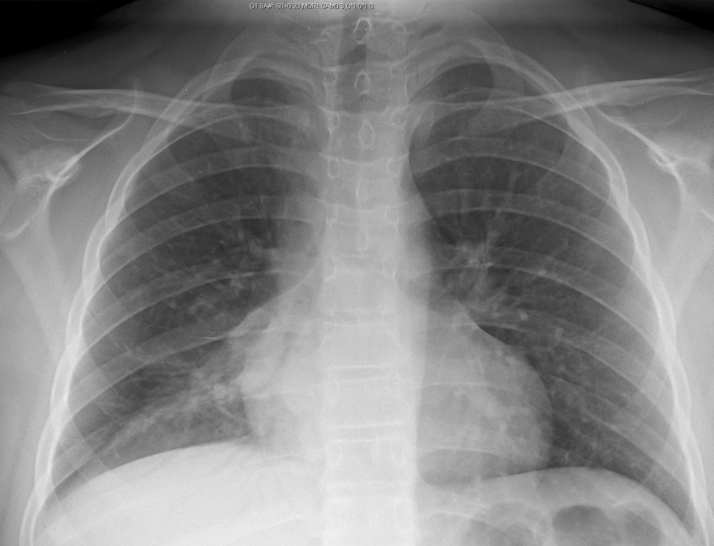

Inspiration

Deeper inspirations show more lung and result in better overall images with less haziness at the lung bases and less enlargement of the heart and mediastinum. A good inspiration on a PA CXR shows at least 9 posterior ribs.

The following films were of the same patient and taken using the same AP projection. The image on the left is a poor inspiratory effort (ribs 1-6), while in the film on the right, the patient achieved a much deeper inspiration on the bottom xray (ribs 1-10).

Poor Inspiratory Effort Good Inspiratory Effort